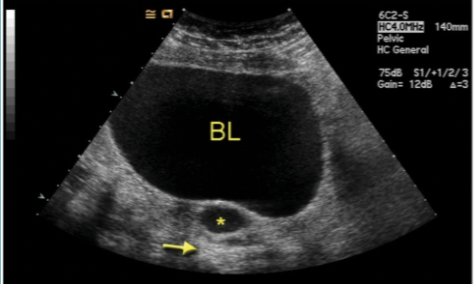

Cervical Stenosis

Stenosis of the uterine cervix is the pathologic narrowing of the uterine cervix

Defined as cervical narrowing that prevents the insertion of a 2.5 mm wide dilator

If the cervical stenosis is severe enough it may result in proximal obstruction resulting in:

hematometra → women of childbearing age with cervical stenosis are less likely to show evidence of hematometra than postmenopausal patients

hydrometra

pyometra

Cervical Stenosis Diagnosis:

Ultrasound

thickened or normal endocervix appearance

may have hydrometra and/or hematometra

cervix may be normal in appearance

uterine cavity may be fluid distended

further complications such as hematosalpinges may be visualized